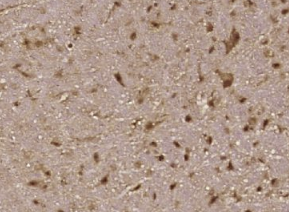

多聚甲醛固定,石蜡包埋(小鼠脑);用柠檬酸钠缓冲液(PH6.0)煮沸15min;用3%过氧化氢阻断内源过氧化物酶20分钟;阻断缓冲液(正常山羊血清)37℃30min;用磷酸-B-RAF(Ser4)孵育抗体。46))多克隆抗体,未结合,1:400,4°C下过夜,然后根据SP试剂盒(兔子)说明和DAB染色进行操作。